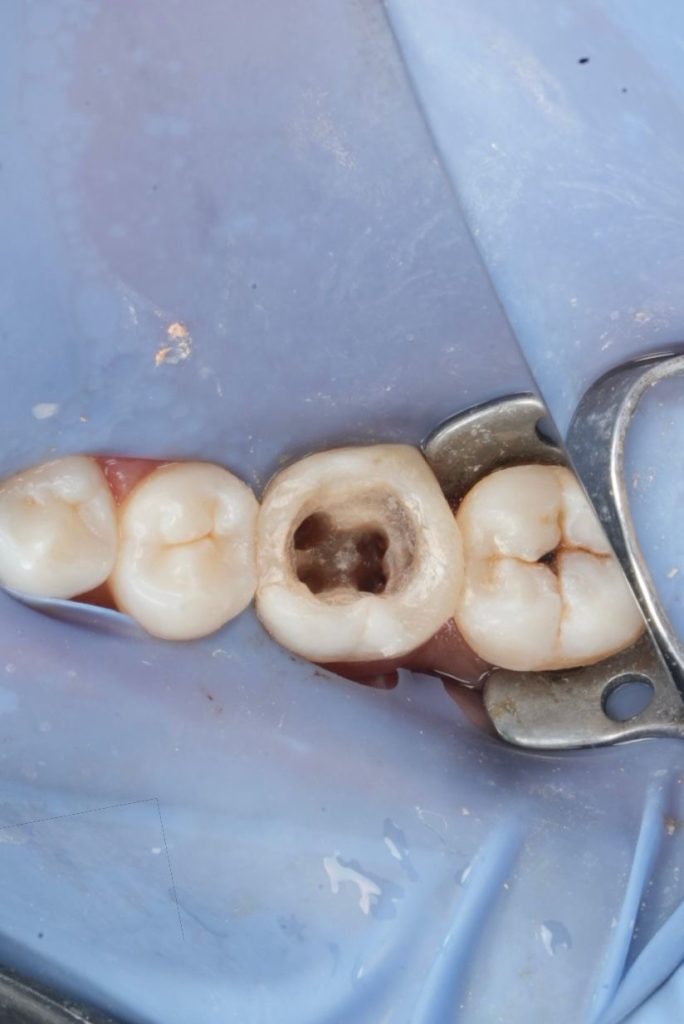

Clinical and Radiographic Findings

- Inadequate root canal obturation with voids.

- Missed canal anatomy suspected.

- Overhanging proximal restoration and subgingival distal margin.

- Associated periapical radiolucency.

- Compromised coronal seal.

- Thick secondary dentin and occlusal attrition pattern.

Endodontic Retreatment

- Rubber dam isolation applied throughout the procedure.

- Existing composite removed; defective margins corrected.

- Previous root filling material removed using rotary retreatment files and solvents.